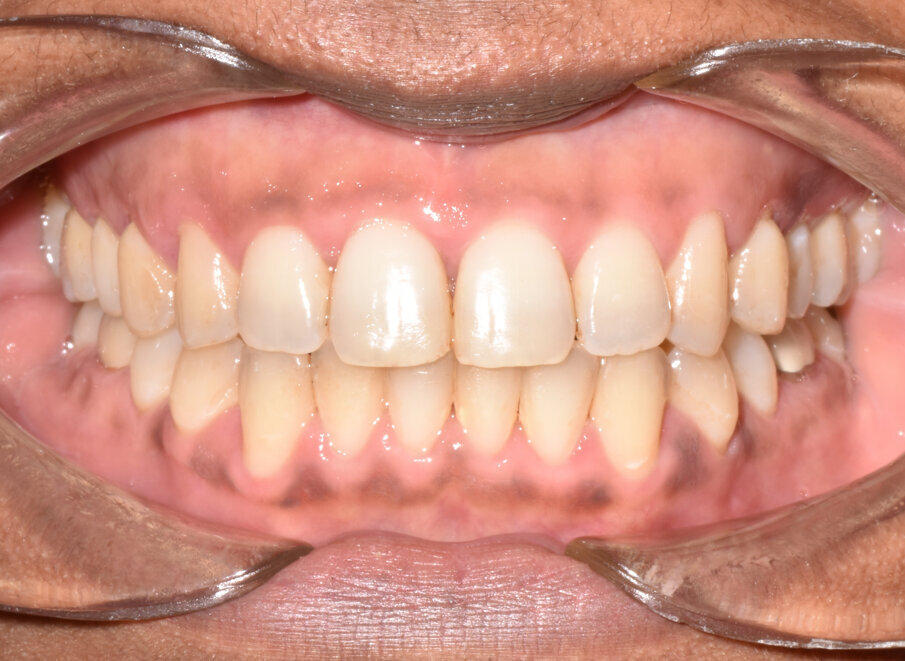

The 31-aligner Spark treatment concluded in five appointments over 7.75 months of active treatment without the need for TADS or refinement aligners. The patient’s excellent compliance was an important factor in the results achieved. Post-treatment photographs demonstrate correction of her Class III, crowded, anterior open bite malocclusion. (Figs. 16-23)

The actual tooth movement closely matched the predicted movement of the digital treatment plan. (Fig. 24) The 31 aligners used with no refinements and the 7.75-month treatment duration are significant.